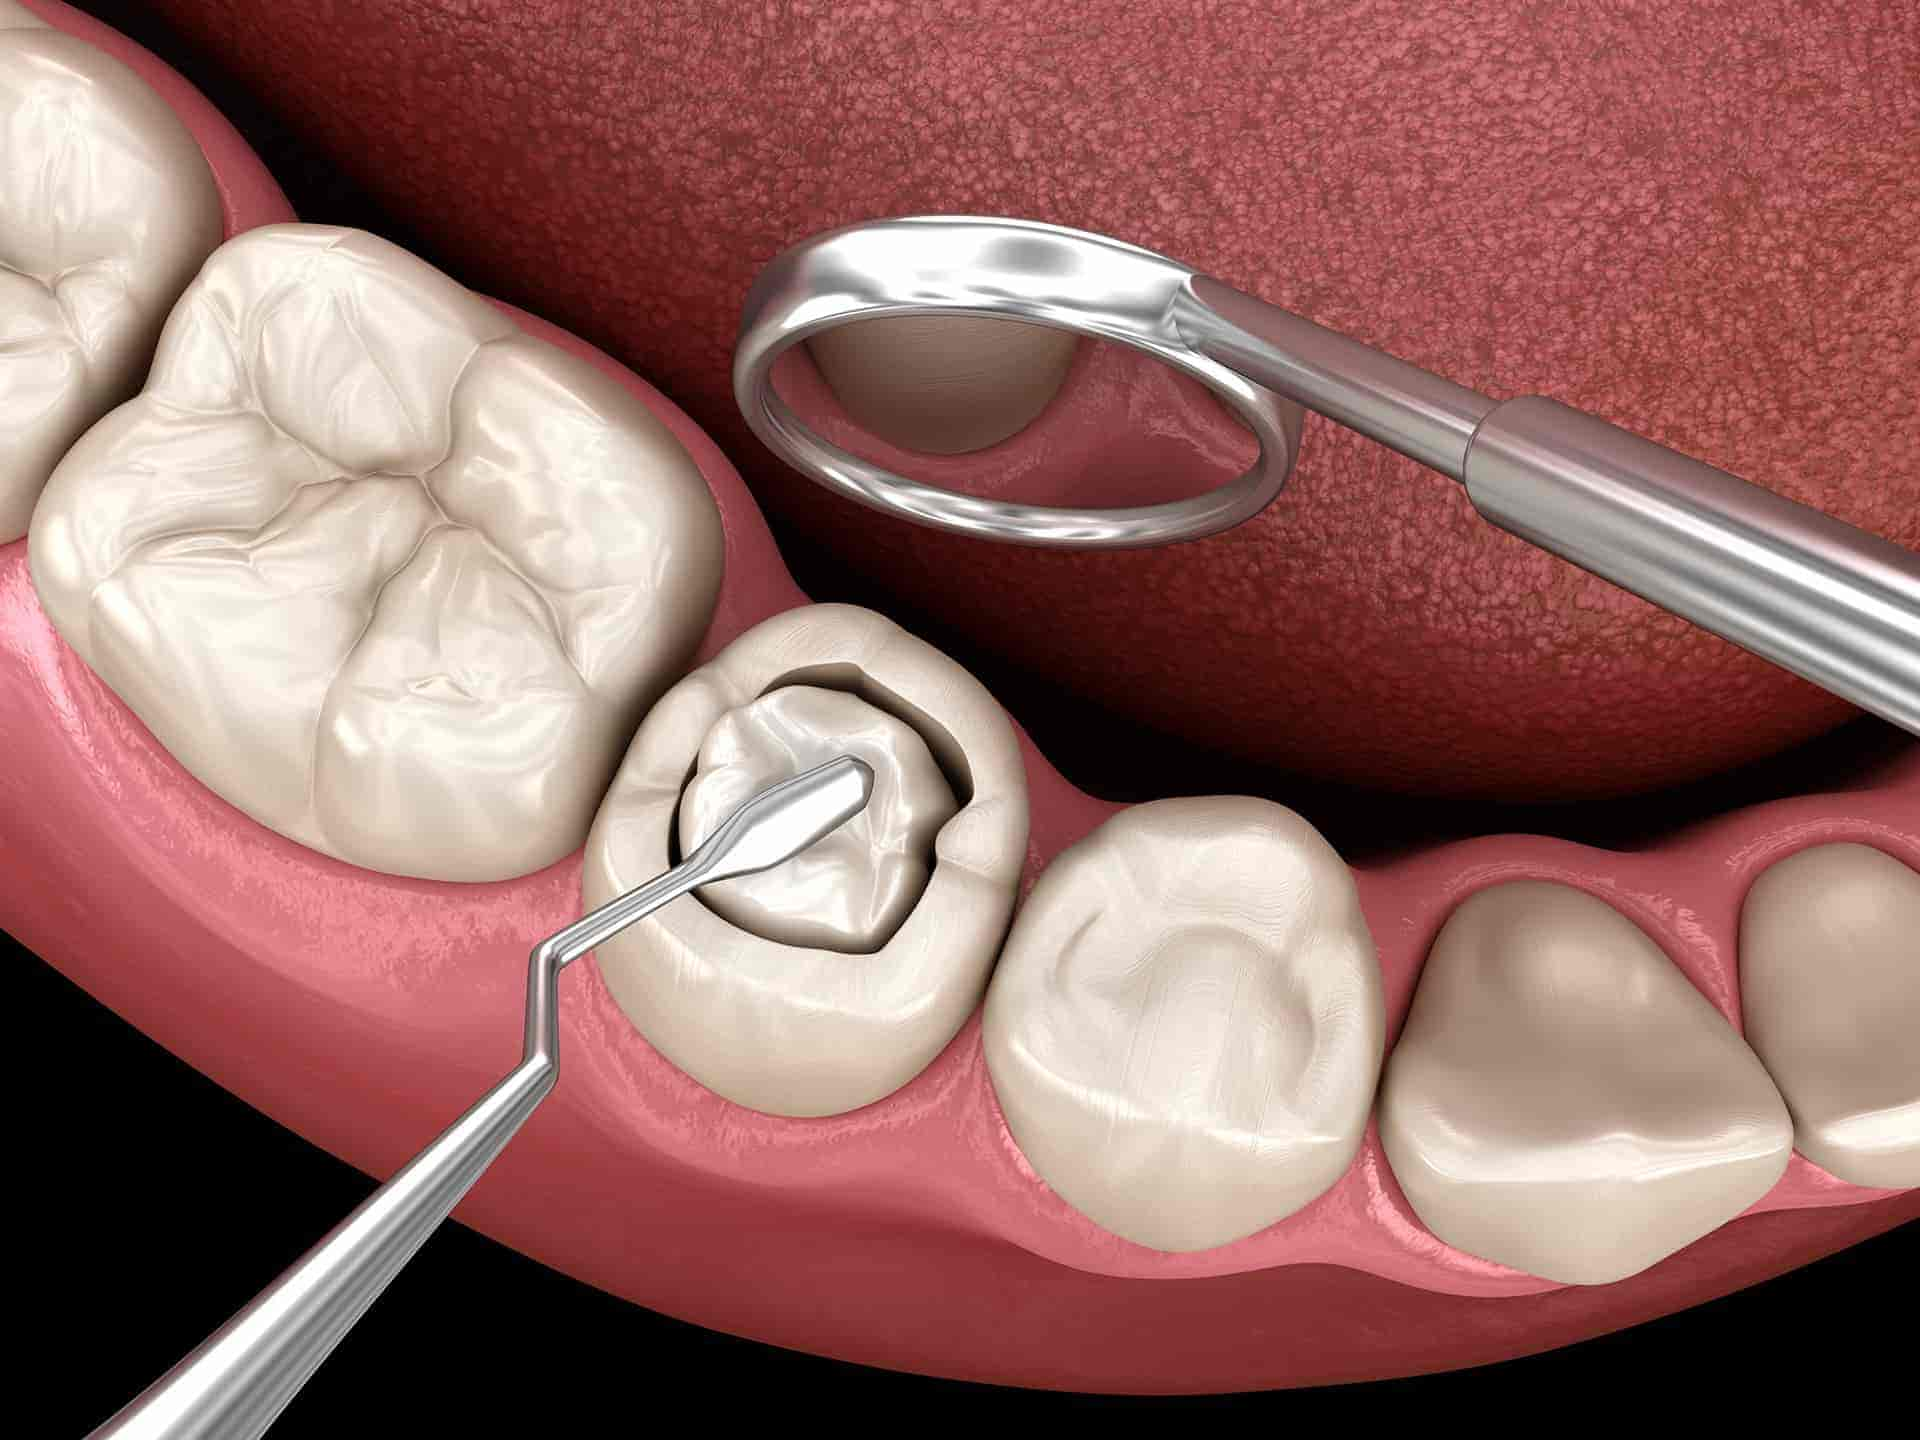

Endodoncija je postupak uklanjanja infekcije i oštećenog tkiva iz kanala korena, čime se čuva prirodan zub i sprečava dalje oštećenje. Tretman je precizan, bezbolan i efikasan, a za najbolje rezultate koristimo moderne tehnologije i savremene metode lečenja.

Restauracija zuba oštećenih karijesom. Nakon uklanjanja zaraženog tkiva, zub se nadoknađuje kompozitnim ili drugim savremenim materijalom, čime se obnavljaju funkcija, čvrstoća i estetski izgled zuba.